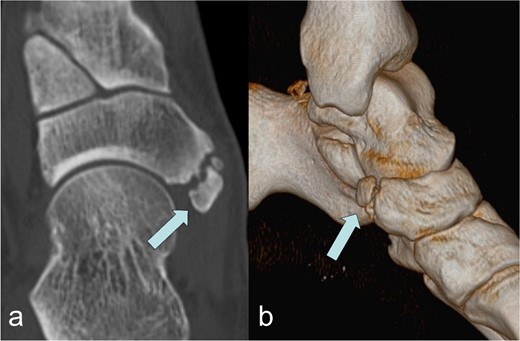

A 53-year-old man with a body mass index of 22.3 kg/m2 reported severe, load-dependent pain (6 out of 10 on the VAS) in the left foot, which had increased over the past two months. Light jogging as a recreational sport was no longer possible due to pain, and no trauma was recalled. Clinically, there was a mild pes planovalgus, with slight swelling and warmth medioplantarly and distal to the medial malleolus along the course of the tibialis posterior tendon. A marked point tenderness was noted, and forced dorsiflexion was severely painful. Conventional radiographs showed a triangular Type II Os tibiale externum at the typical site, measuring approximately 10.5 x 6 mm (Fig. 1a and b). Additional CT imaging in the axial plane with coronal reconstruction and subsequent 3D reconstruction (Fig. 2a and b) revealed a Type II Os tibiale externum with a distinct synchondrosis gap to the navicular bone. An MRI showed central inflammatory reaction in the synchondrosis and significant perifocal soft tissue edema of the Os tibiale externum with involvement of the tibialis posterior tendon, with no tendon rupture detected (Fig. 3a–d).

Image of the Os tibiale externum Type II in the coronal reformatted CT scan (a) and in the 3D representation (b); the ossicle is marked with an arrow.